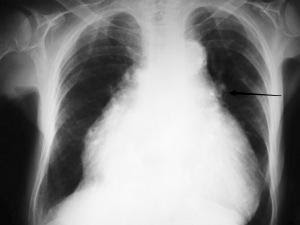

CXR

Common findings are cardiomegaly and effusions. Chest x-ray (CXR) findings may lag by 12 hours from onset of symptoms, and subsequently CXR findings may persist for several days despite clinical improvement. 1 out of 5 patients admitted for CHF exacerbations showed lack of any pulmonary congestion on CXR.

Cardiomegaly is defined as a cardiothoracic ratio greater than 50% diameter. Patients with diastolic failure may have normal heart size.

Image 7: By Nevit Dilmen (Own work) [GFDL](http://www.gnu.org/copyleft/fdl.html) or CC BY-SA 3.0 (http://creativecommons.org/licenses/by-sa/3.0)%5D, via Wikimedia Commons

Additional CXR findings include:

- Peribronchial cuffing – thickened bronchial walls secondary to edema. Indicated by arrow in above image.

- Perihilar congestion – large hila with indistinct margins suggest pulmonary vasculature edema. Indicated by the two arrows in the image below.